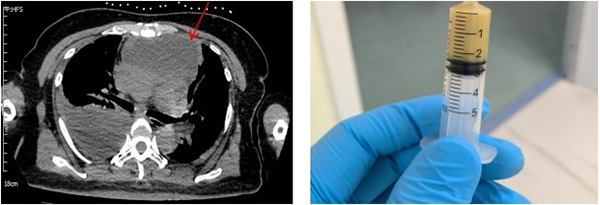

胸外科主任崔健在充分了解患者病情后,对病情进行了全面评估,即刻联系放射科安排CT引导下前纵膈肿物穿刺术,抽吸出黄色脓性坏死物,确诊疾病为“纵膈脓肿”,并指示病情危重,需进行急诊手术治疗,迅速联系麻醉科。在麻醉科的大力配合下即刻开展了手术。由于患者纵膈脓肿合并右侧脓胸,单纯纵膈清创引流不能解决右侧胸腔感染,遂决定在胸腔镜下行右侧脓胸清除术+前纵膈切开引流术。术中可见右侧胸腔大量脓性坏死物,吸出胸腔内脓液约650ml,紧接着打开前纵膈,吸出脓性坏死物约200ml,后进行了彻底的冲洗,在紧锣密鼓的3小时手术后,患者平安返回病房,最终顺利出院。

▲CT引导下纵膈肿物定位以及穿刺后抽吸坏死物质